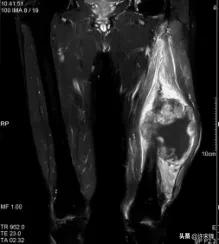

MRI检查时,T1WI表现为和软组织等信号或接近等信号,T2WI表现为高信号,如有坏死表现为更高信号区,如有出血,在T1WI、T2WI上均表现为高信号,增强后有强化表现。

男,65岁,左大腿横纹肌肉瘤,侵及左股骨